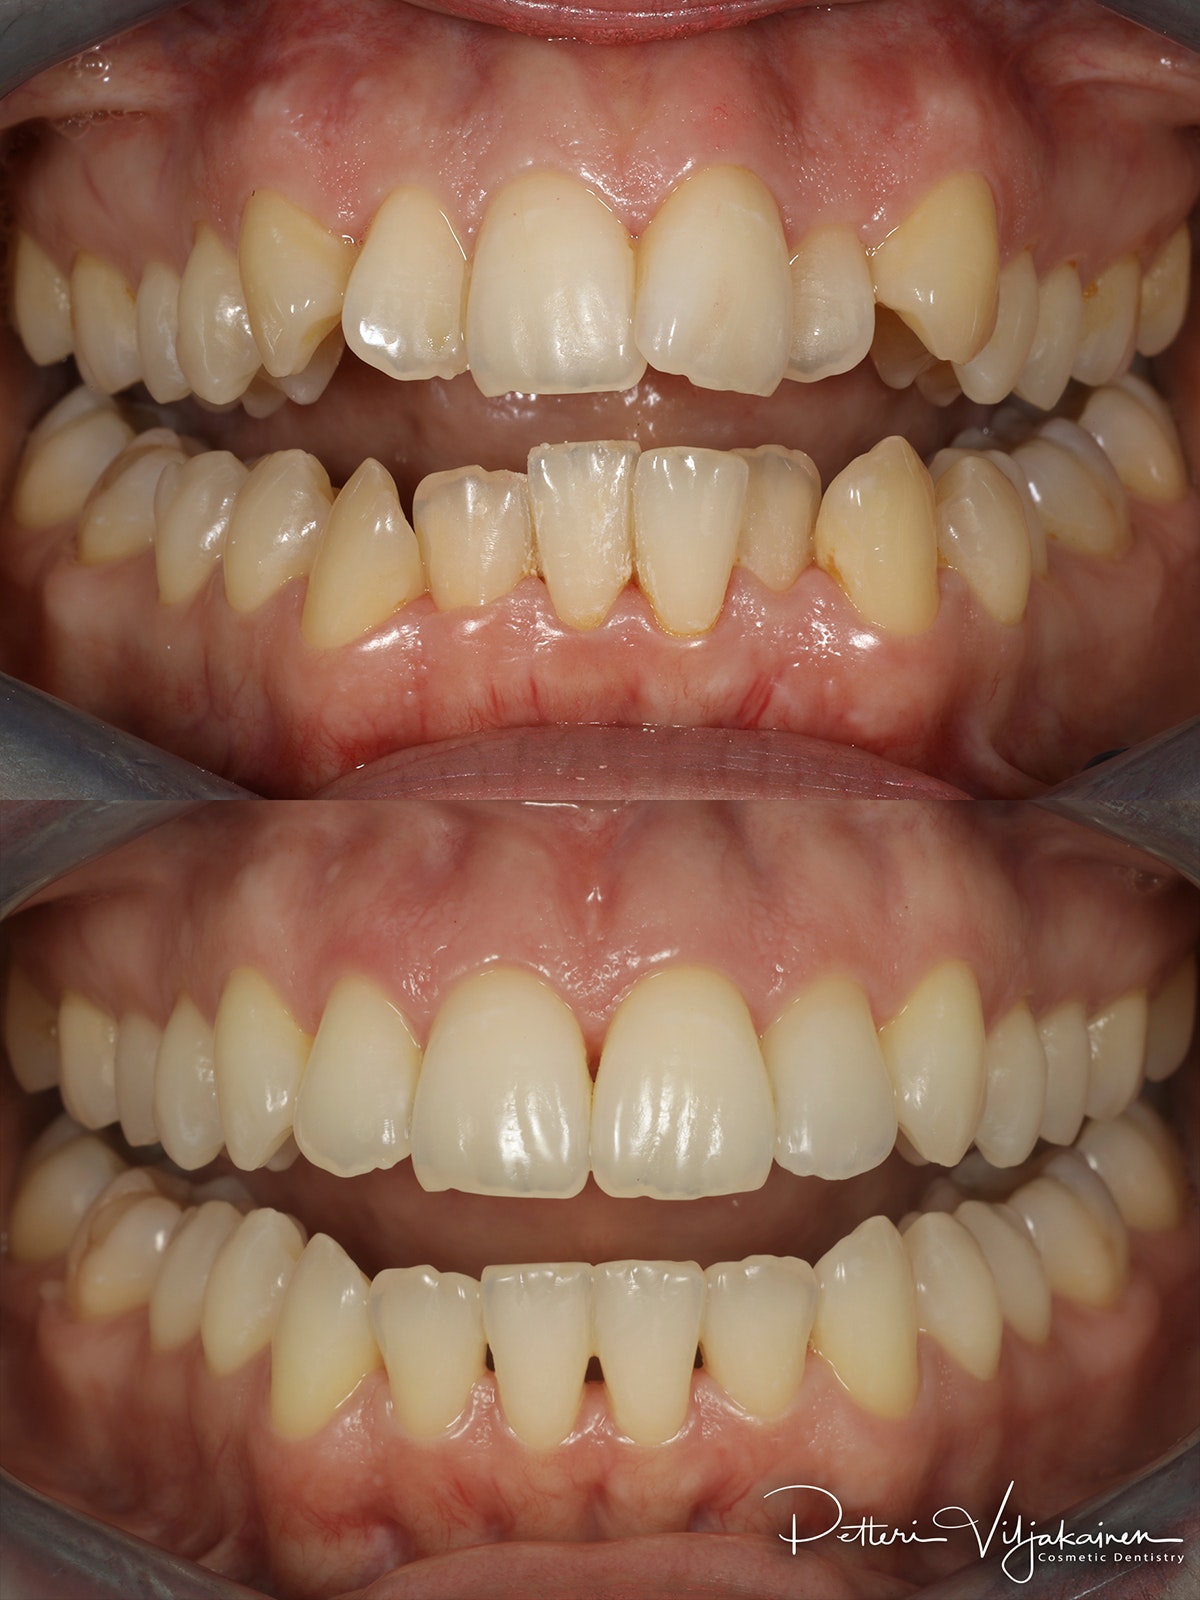

Alla suorittamiani hoitoja ja esimerkkejä siitä minkälaisia purentavirheitä voi korjata.

10 kk hoito (Comprehensive). Aavistus esteettistä muovia lisätty yläkulmahampaisiin hoidon jälkeen.